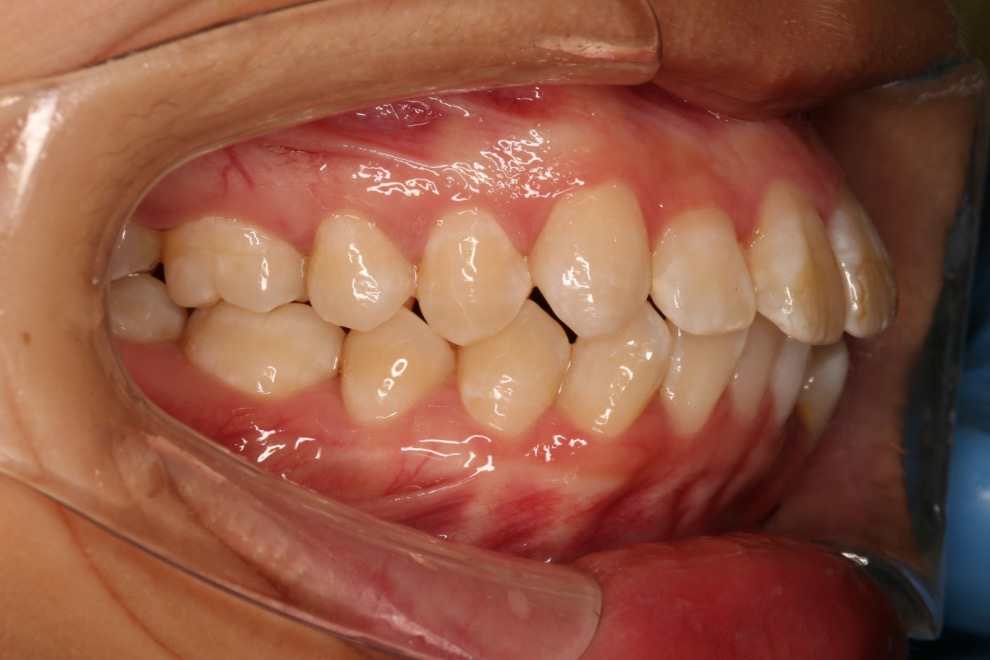

• 磨牙,尖牙I类关系,中线齐

• 上下牙列中度拥挤

• 上下前牙唇倾

IntraoralExamination(2016-08.31,Wu)

2018.11.14  术后磨牙尖牙I类关系,中线齐,覆合,覆盖正常